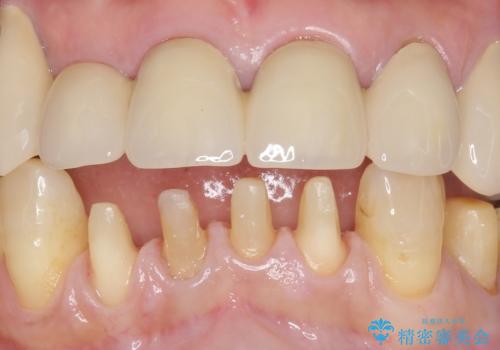

- 下の前歯が欠けてぐらぐらすることを主訴に来院された患者様です。

以前行った奥歯の治療により下顎前歯の動揺は改善傾向にあり顕著ではなかったのですが、欠けて黒くなっていることと少しの動揺が気になるとのことでした。

元気なうちに治療しておきたいという患者様の強いご希望により、下顎前歯の連結補綴と欠けている小臼歯の補綴治療を行いました。